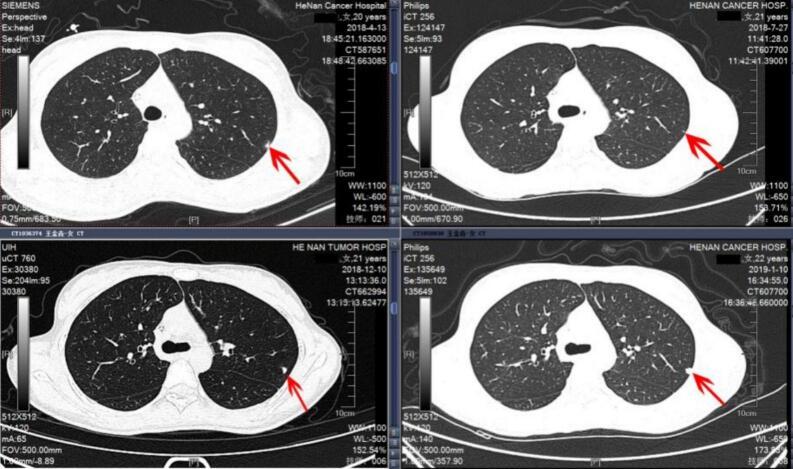

We retrospectively analyzed clinical data from 126 osteosarcoma patients aged 20 years or younger who were treated at Henan Cancer Hospital between January 2012 and January 2022. Pre-treatment thin-slice computed tomography (CT) scans of lung were used to categorize patients into three groups: no IPN (n = 100), solitary IPN (n = 16), and multiple IPNs (n = 10). Baseline characteristics, primary tumor parameters, treatment modalities, and follow-up data were collected. Univariate and multivariate analyses were conducted to assess risk factors and survival outcomes.

我们回顾性分析了2012年1月至2022年1月在河南省肿瘤医院接受治疗的126例20岁及以下骨肉瘤患者的临床资料。使用治疗前肺部薄层计算机断层扫描(CT)将患者分为三组:无IPN(n = 100)、孤立性IPN(n = 16)和多发性IPN(n = 10)。收集基线特征、原发肿瘤参数、治疗方式和随访数据。进行单因素和多因素分析以评估危险因素和生存结果。